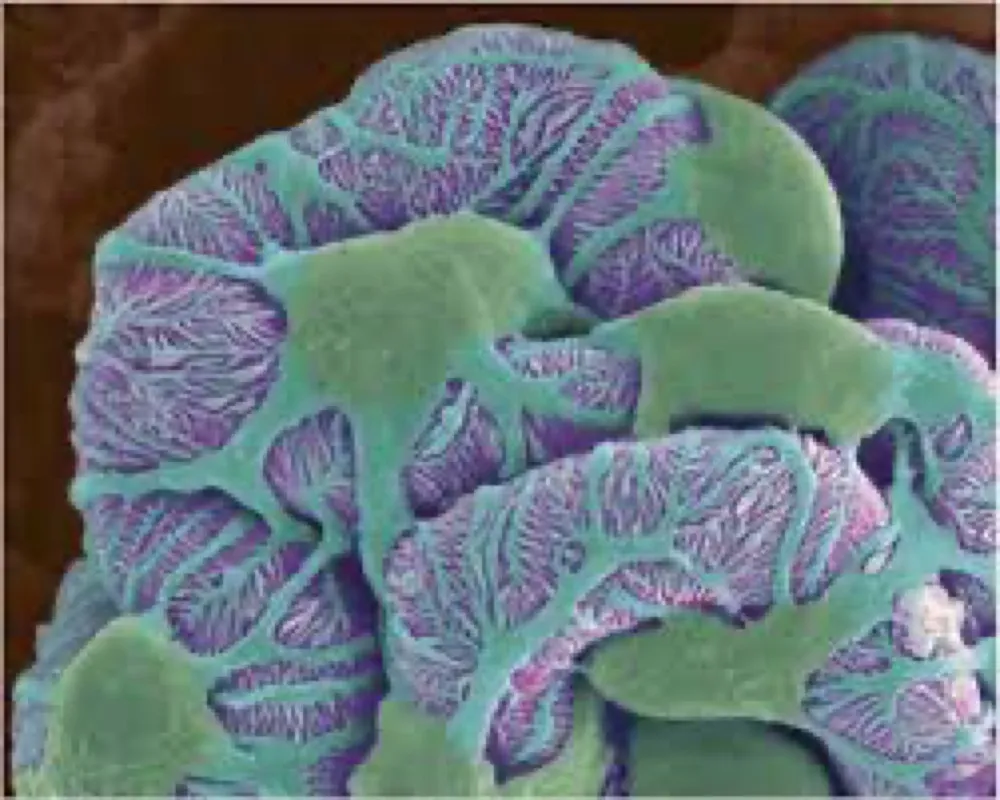

Injúria Renal Aguda (revisão Lancet 2025)

Injúria Renal Aguda (revisão Lancet 2025)